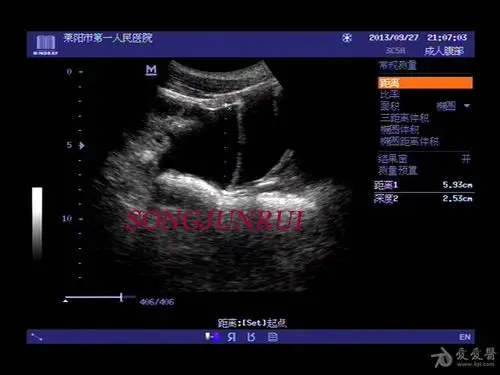

【超声】肝破裂超声,请战友欣赏

肝ca自发性破裂 - 超声医学讨论版 - 爱爱医医学论坛

超声入门贴157肝破裂